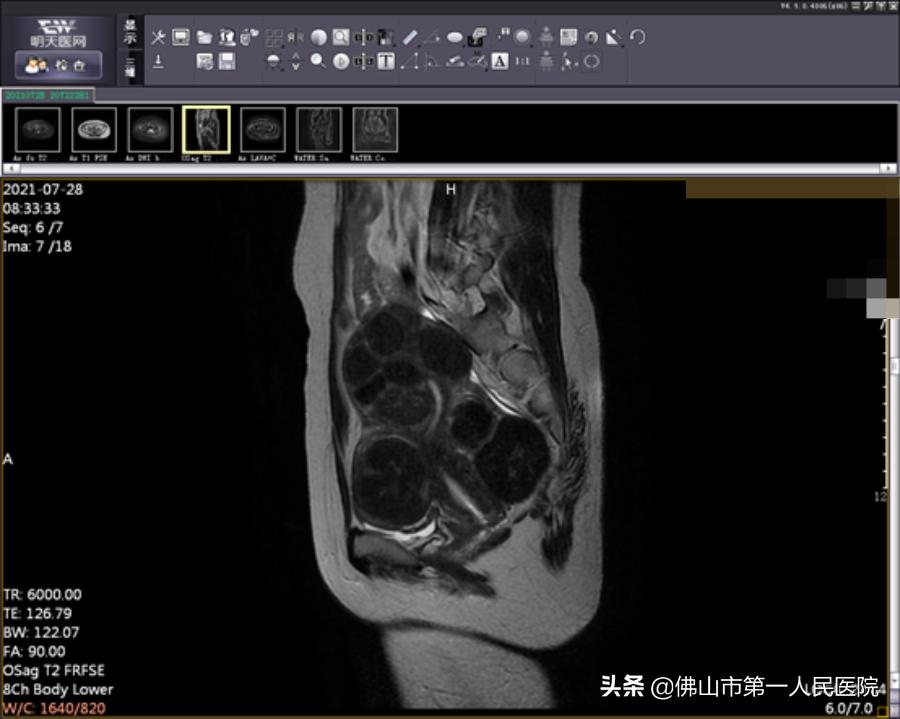

术前图像

经充分检查和术前评估,陆女士符合“海扶刀”治疗指征。由于陆女士子宫肌瘤分布于于肌壁间、黏膜下和浆膜下,数量较多,大小不一,我院海扶中心潘智茵副主任及其团队结合多年“海扶刀”治疗经验,制定了宫腔镜检查联合“海扶刀”手术的治疗方案。

2021年7月,医生为陆女士行宫腔镜检查,子宫内膜未见明显异常,粘膜下肌瘤向宫腔凸起小于二分之一,大于二分之一位于肌壁间。宫腔镜检查术后1天患者无明显阴道流血,遂行海扶刀手术。

术后图像(海扶使肿瘤组织发生凝固性坏死)

海扶刀手术时长2小时50分钟,治疗时间25分钟。王女士表示术中无明显不适,术后数小时后就能下床正常活动。术后复查磁共振提示消融效果满意,术后月经量正常,术后复查MRI肌瘤消融满意。